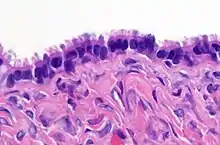

High magnification micrograph of a Brenner tumor, a type of surface epithelial-stromal tumor. H&E stain.

Brenner tumour. H&E stain.

Brenner tumors are uncommon surface-epithelial stromal cell tumors in which the epithelial cell (which defines these tumors) is a transitional cell. These are similar in appearance to bladder epithelia. The tumors may be very small to very large, and may be solid or cystic. Histologically, the tumor consists of nests of the aforementioned transitional cells within surrounding tissue that resembles normal ovary. Brenner tumors may be benign or malignant, depending on whether the tumor cells invade the surrounding tissue.